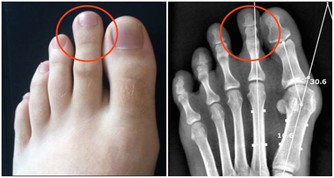

3、 尿酸

這五種毒素是女性衰老催化劑,必須盡快排出

尿酸是人體產生的一種物質,這種物質一般在人體中濃度是一樣的,但是如果出現濃度升高的話,可能出現對身體有一定的危害,人體尿酸偏高會對腎臟造成一定的影響,出現痛風性腎病,早期僅表現為間歇性蛋白尿,但只是隨著病情的發展,晚期可發生腎功能不全,部分患者會出現尿酸性腎結石當結石引起梗阻時導致腎積水,腎盂腎炎,腎積膿等。通常腎不好的女性會臉色發黃,嘴唇蒼白,自然也就更加顯老了。